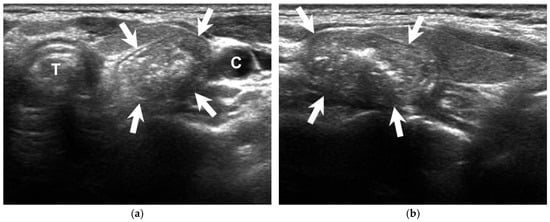

How Soda Ingestion Facilitates the Distinction between a Killian–Jamieson Diverticulum and a Malignant Thyroid Nodule